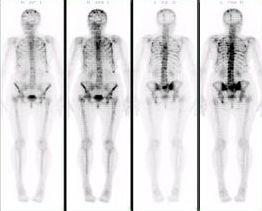

1.繼發性骨腫瘤骨顯像對於轉移性骨腫瘤的診斷具有很高的靈敏度。在腫瘤轉移的早期就伴有局部骨組織代謝異常,因此骨顯像發現惡性腫瘤骨轉移灶可較X線攝片早3-6個月。成人骨轉移多見於乳腺癌、肺癌等,骨顯像應為此類病人的常規檢查項目之一。惡性腫瘤患者如主訴有固定的骨骼疼痛,但實驗室各項檢查及X線攝片等顯示正常結果時,應做骨顯像以早期發現轉移病灶。

2.原發性骨腫瘤攝取骨顯像劑比正常組織或良性骨腫瘤高,動脈相亦有早期充盈,血池相呈現局部充血,延遲相表現為局部放射性異常濃聚。惡性原發性骨腫瘤以成骨肉瘤、Ewing氏肉瘤及軟骨肉瘤的惡性程度最高。骨顯像有較高的診斷價值,但屬何種類型的腫瘤,臨床需結合年齡、病變部位、病變數量、顯像圖的形態等綜合分析。某些原發性骨腫瘤的骨外轉移灶(通常是肺轉移)也能濃聚骨顯像劑,骨顯像對於成骨肉瘤肺轉移的診斷遠較X線診斷敏感。以溶骨性改變為主的原發性骨腫瘤如多發性骨髓瘤,病變組織對顯像劑的攝取無明顯增加,故診斷靈敏度不及X線檢查。一般來說,骨顯像顯示病灶的範圍比X線片所顯示的要大,對已確診的原發性骨腫瘤,骨顯像能顯示骨質代謝異常的範圍,有助於手術方案的制定和合理安排放療照射野的大小以及估計治療後的效果。